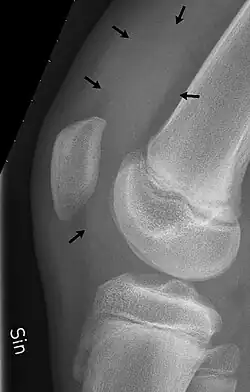

The knee bursae are the fluid-filled sacs and synovial pockets that surround and sometimes communicate with the knee joint cavity. The bursae are thin-walled, and filled with synovial fluid. They represent the weak point of the joint, but also provide enlargements to the joint space.[1] They can be grouped into either communicating and non-communicating bursae or, after their location – frontal, lateral, or medial.

Frontal

In front, there are five bursae:

- the suprapatellar bursa or recess between the anterior surface of the lower part of the femur and the deep surface of the quadriceps femoris.[2] It allows for movement of the quadriceps tendon over the distal end of the femur. In about 85% of individuals, this bursa communicates with the knee joint. A distension of this bursa is therefore generally an indication of knee effusion.[3]

- the prepatellar bursa between the patella and the skin[2] It allows movement of the skin over the underlying patella.

- the deep infrapatellar bursa between the upper part of the tibia and the patellar ligament.[2] It allows for movement of the patellar ligament over the tibia.[4]

- the subcutaneous (or superficial) infrapatellar bursa between the patellar ligament and skin.[2]

- the pretibial bursa between the tibial tuberosity and the skin.[2] It allows for movement of the skin over the tibial tuberosity.[4]